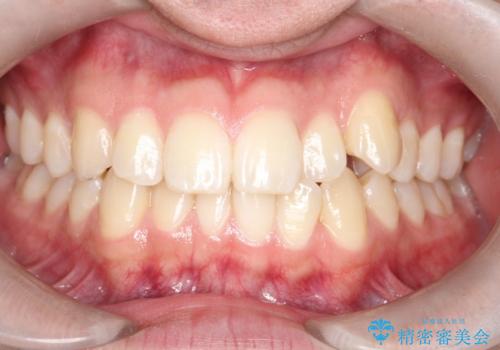

- 八重歯が気になるとのことでご来院されました。お口の中を確認すると、上の前歯がスペース不足で押し出され、少し前に出ている状態でした。抜歯せずに整えるため、奥歯を少しずつ後ろに動かしながら(遠心移動)、歯と歯の間をわずかに削るIPRを行ってスペースを作ることにしました。また、上下の噛み合わせを整えるために2級ゴム(エラスティック)を使用する方針を立てました。

マウスピースを段階的に交換しながら、奥歯を少しずつ後ろへ動かし、八重歯がきれいに並ぶよう調整しました。前歯の突出感を抑えるためにIPRを行い、スムーズに配列。さらに、2級ゴムを活用して噛み合わせも改善しました。治療後は、自然な歯並びになり、笑顔に自信が持てるようになったと喜んでいただきました。